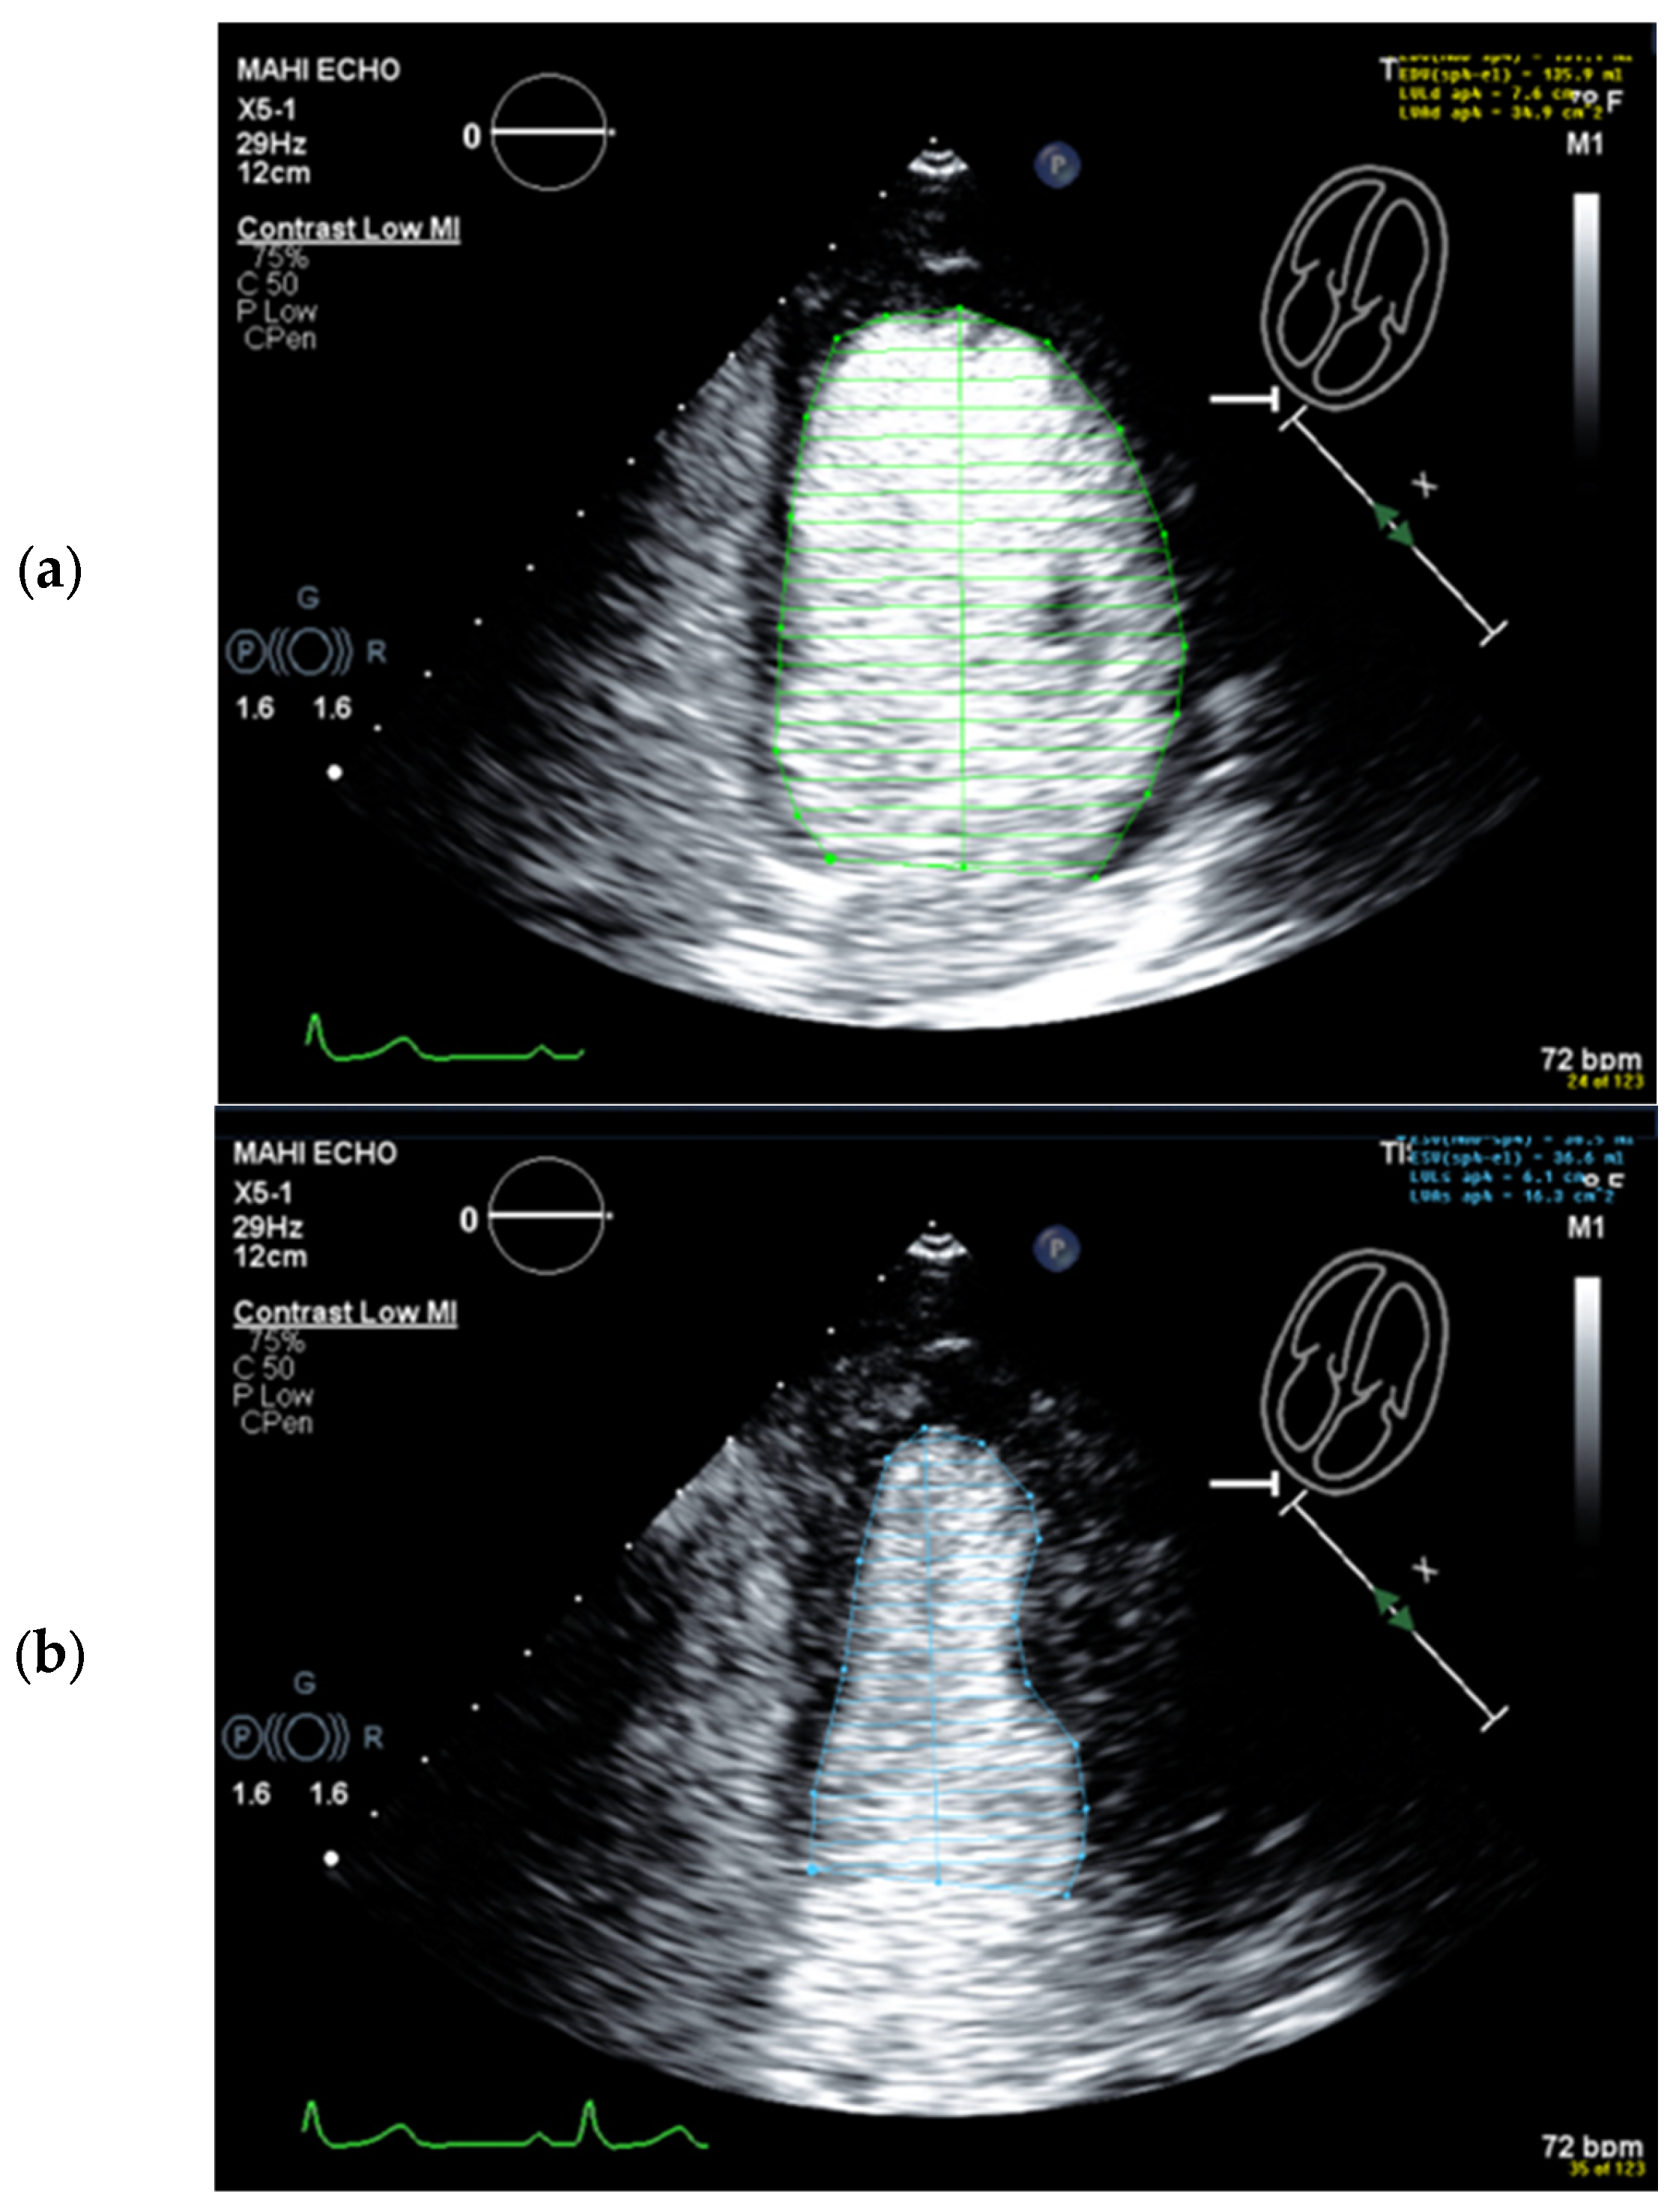

Selection of Foreshortened Loops

Selection of False End-Diastolic and End-Systolic Frames

Starting Point for the LV Contour at the Mitral Valve Ring Is Incorrect

Wrong Contour/Papillary Muscle

| 1 | Select unforeshortened loops avoid 4-chamber views, which include anterolateral papillary muscles | When several loops are available, select the one with the longest long axis which impairs tracing of the lateral LV wall |

| 2 | Select the end-diastolic frame | The first frame after mitral valve closure or the largest LV cavity |

| 3 | Trace the LV border: end diastole | Starting on the septal mitral ring (4-chamber view) and inferior mitral ring (2-chamber view), following the dark/bright interface until the lateral/anterior mitral ring The start and end points of the contour at the mitral ring should be connected by a straight line TIP The mitral leaflets may be obscured by the UEA. Then look for the bright signals of the mitral ring, which are more clearly delineated and follow the entire loop rather than only in the end-diastolic frame. |

| 4 | Select the end-systolic frame | Smallest cavity—the mitral valve closure may be obscured by the UEA! TIP: When scrolling through the systolic frames of the loop, look for the frame when the cavity becomes larger. The frame before it is the end-systolic frame. |

| 5 | Trace the LV border: end systole | Starting on the septal mitral ring (4-chamber view) and inferior mitral ring (2-chamber view), following the dark/bright interface until the lateral/anterior mitral ring The start and end points of the contour at the mitral ring should be connected with a straight line |

| 6 | Check the LV length (distance between the middle of the line connecting the mitral ring and the apex) | When the difference in diastolic LV length between 4- and 2-chamber views is <0.5 cm, no major foreshortening can be assumed When the difference is >5 mm, the recording of the view with the shorter LV length is probably not optimal. The other recordings of this view should be reviewed to find the one with the longest LV [59]. |